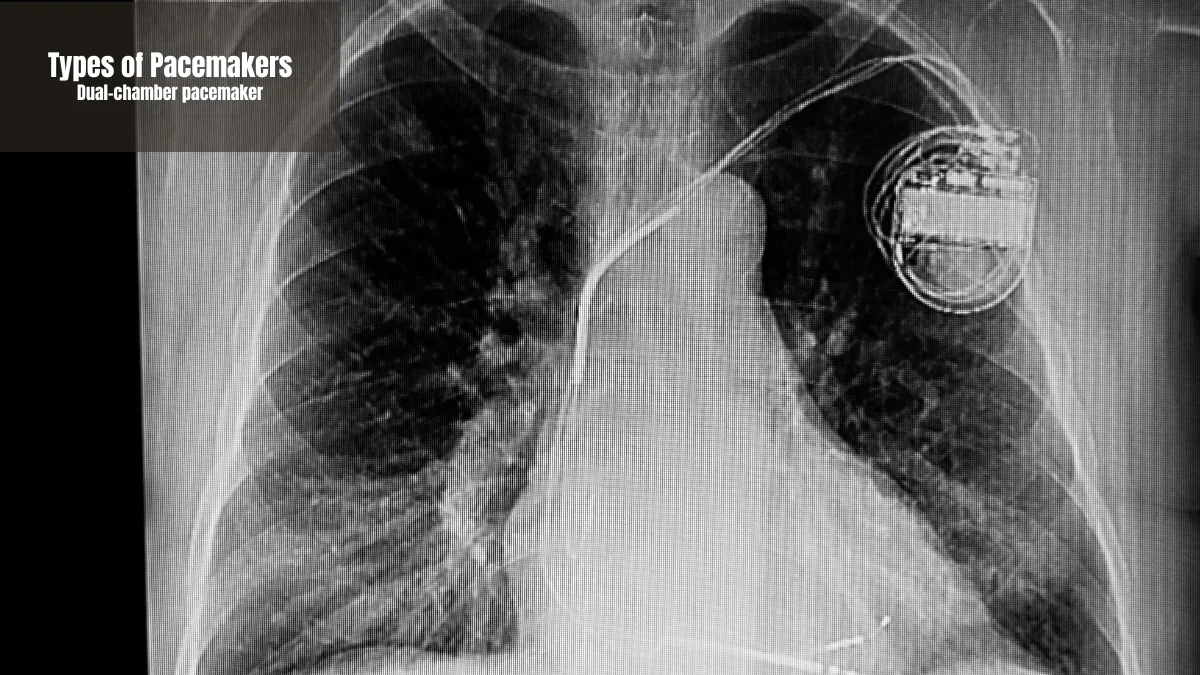

Dual-chamber pacemaker

A dual-chamber pacemaker is a type that uses two wires to stimulate the right atrium and right ventricle. The goal is to synchronize blood pumping in both chambers of the heart at the same time.

Heart rhythm problems that require better coordination between the heart chambers are best treated with this device. This device will reduce symptoms of dizziness or fatigue due to more efficient blood flow.